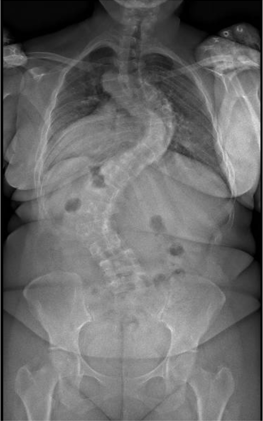

Sagittal alignment of a 26-year-old volunteer (A) and a 68-year-old volunteer (B). The figure is representative of the volunteer population as it shows a higher thoracic kyphosis in the older volunteer while maintaining the odontoid-knee distance by using compensatory mechanisms such as slight knee flexion and cervical extension.

We found that asymptomatic volunteers used compensatory mechanisms such as slight pelvis retroversion, knee flexion, and neck extension to maintain an aligned sagittal posture with their head centered over their knees (Not the pelvis).

In asymptomatic volunteers, sagittal alignment parameters saw a slow and steady change across age groups most exemplified by an increase in Thoracic kyphosis, while lumbar lordosis did not show a significant decrease across age groups.